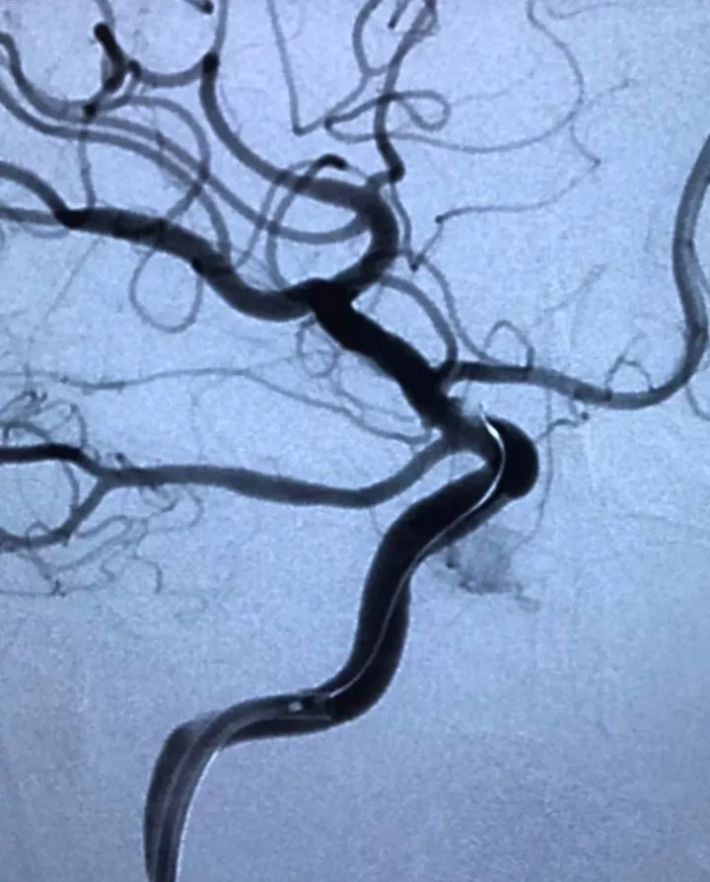

右颈内动脉工作位造影

瘤太小了,放大看(箭头所指)